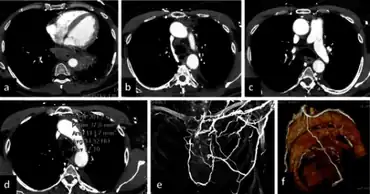

Acute mediastinitis can be confirmed by contrast x-rays since most cases of acute mediastinitis are due to esophageal perforation. Other studies that can be used include endoscopic visualization, Chest CT scan with oral and intravenous contrast.

With regards to CT Imaging, the extent of involvement of the mediastinum can be evaluated. Therefore, acute mediastinitis can be classified into three categories:[9]

- diffuse mediastinitis

- isolated mediastinal abscess

- mediastinitis or mediastinal abscess complicated by empyema or subphrenic abscess.